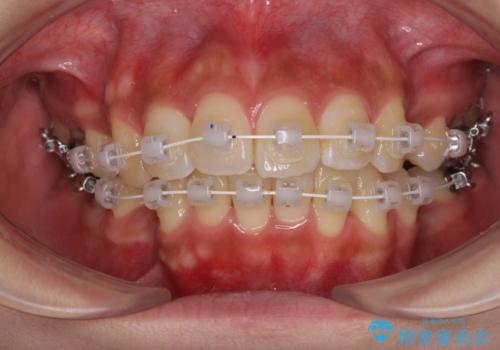

- 審美装置

- 1年11ヶ月

アンカースクリューと補助装置を使用して上顎大臼歯を遠心移動させることで咬み合わせを改善し、更には口元の突出感を改善するために上下左右の小臼歯4本を抜歯し、ワイヤー装置によりデコボコを解消しながら口元の突出感も改善していくこととしました。